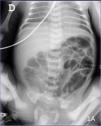

Premature 28-week baby weighing 850g at birth. Red blood cells are transfused due to prematurity anemia at the patient’s 22nd day of life. Twelve hours into the transfusion the patient shows abdominal distension and vomiting of gastric content. The blood test performed showed no alterations in the blood gasometry or elevated parameters of infection. The abdominal X-ray performed showed no signs suggestive of enterocolitis (Fig. 1A), but the abdominal ultrasound performed did show lack of peristalsis and intestinal loops with 2 layers of echogenic foci in the walls (white arrows), a sign indicative of the presence of intraluminal air (Fig. 2A), and echogenic foci in the hepatic parenchyma indicative of gas bubbles inside the portal veins (white arrows), a sign suggestive of portal venous gas (Fig. 2B) oriented as a clinical sign of enterocolitis. The patient remains on a diet and antibiotic therapy is started. The ultrasound looks normal with good disease progression (white asterisks) (Fig. 2C) after the completion of a 14 day course of antibiotic treatment.